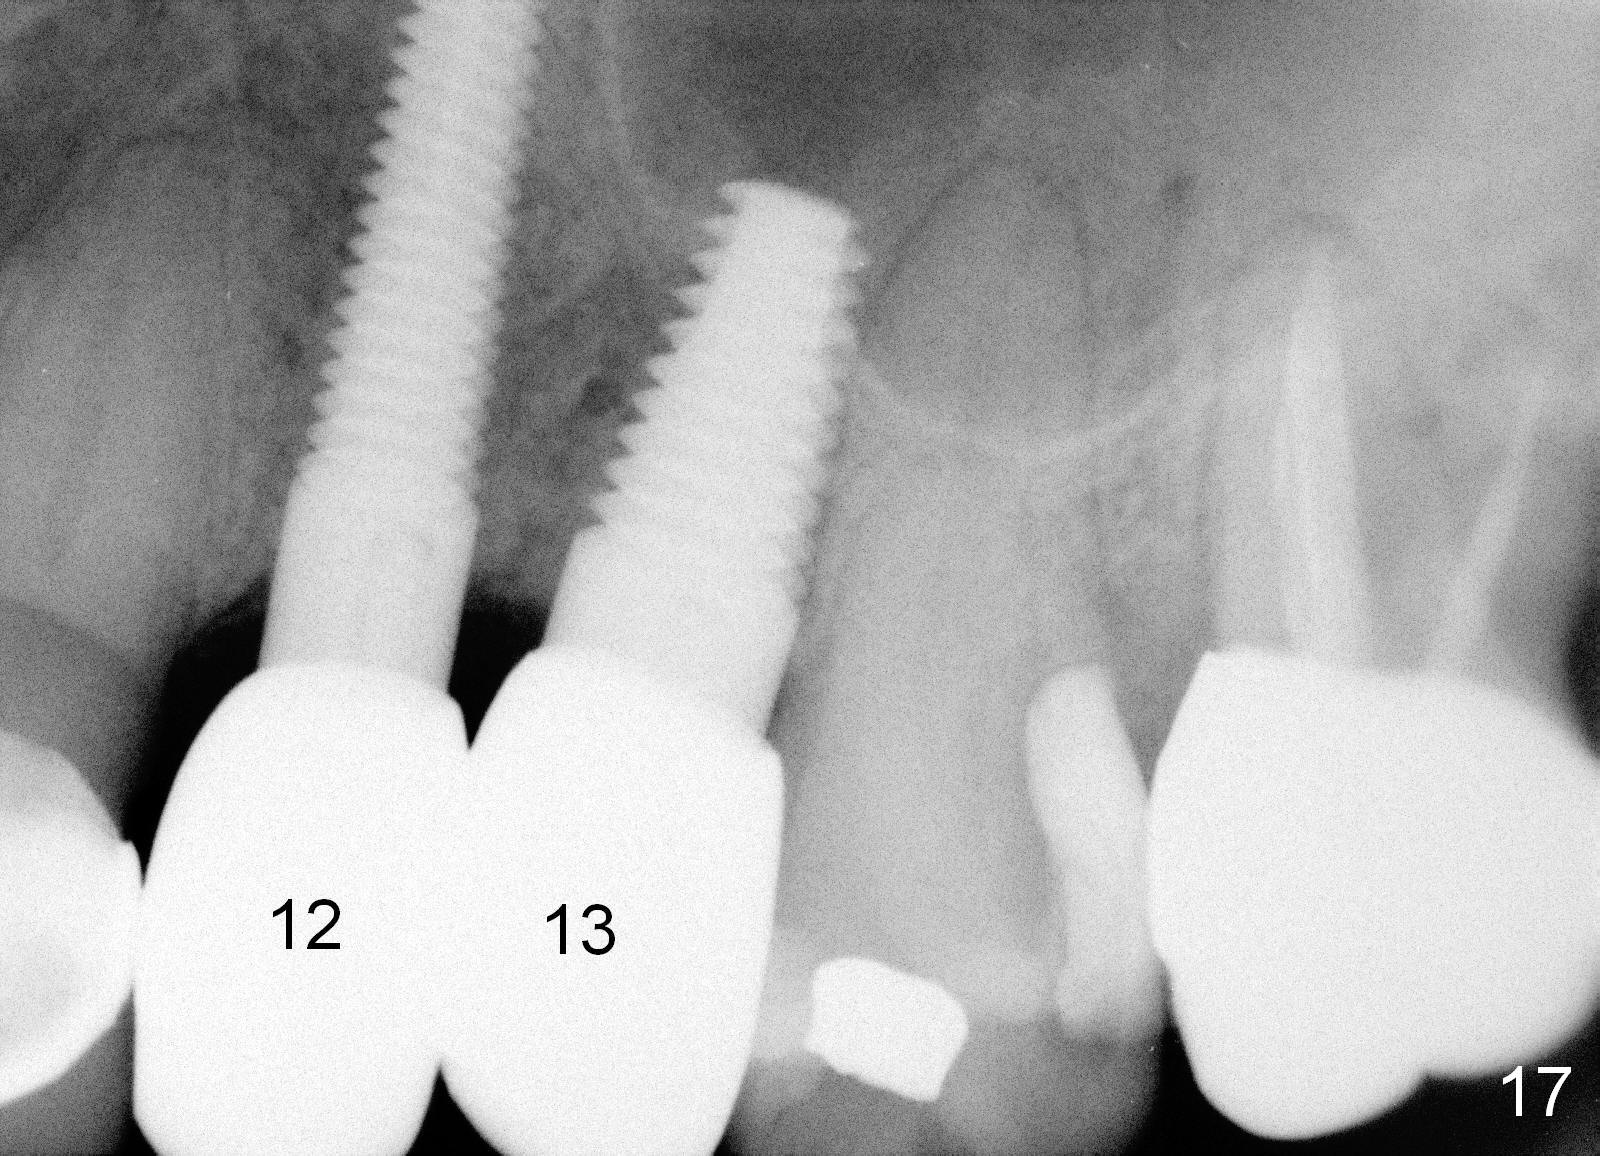

The anterior retainer is kept as a crown at #11 (Fig.2: C), whereas the residual root at the site of #13 is extracted with apical perforation (Fig.3 ^).  It is confirmed by Fig.4 (<).  To close the perforation, an osteotomy is initiated on the palatal wall of the socket with a 2 mm osteotome (Fig.5 insert: circle).  As the osteotomy is being enlarged by a 3 mm osteotome, the bone between the original socket and the osteotomy is being pushed buccally.  The former is being closed (Fig.5).  The osteotomy is finished with combination of osteotomes and reamers.  Fig.6 shows that a 5x14 mm tap is inserted at the site of #13 and that the sinus floor is lifted.  In fact the sinus membrane is partially torn at the osteotomy, which is repaired by insertion of Colla-form Dressing (Impladent), followed by autogenous bone (harvested from reamers) mixed with Osteogen  (Impladent).  A 5x14 mm implant is placed at the site of #13 with insertion torque more than 60 Ncm (Fig.7: I).  An incision is made at the site of #12 to start osteotomy with insertion of a parallel pin (Fig.7 P).  A 3 mm reamer is kept in place for position confirmation (Fig.8 R).  Due to ridge atrophy (Fig.2 arrowheads), a much smaller, but longer implant is placed at the site of #12 (Fig.9: 4x17 mm).  The autogenous bone harvested from #12 osteotomy is placed in the buccal gap of #13, followed by insertion of Colla-form Dressing (Fig.10 M).  To protect the membrane, a short abutment (4x3 mm) is temporarily placed (Fig.9,10 A) and perio dressing (Fig.9 D) is applied around the abutment and the interproximal areas of the neighboring teeth.  Usually perio dressing dislodges around 1 week postop, particularly for a large edentulous space.  In this case, the dressing is quite stable 11 days postop: the abutment (Fig.11 A) appears to contribute to retention of the dressing (D).

Three month follow-up shows that the gingiva and bone heal around these two implants (Fig.13-15).  Crowns are cemented 4.5 months postop (Fig.16).  There is no or minimal bone loss 9 months post cementation (Fig.17, as compared to Fig.15).  The bone is stable around the implants 18 months post cementation (Fig.18 panoramus).  Root canal therapy is done at #14 between the last follow up appointments.